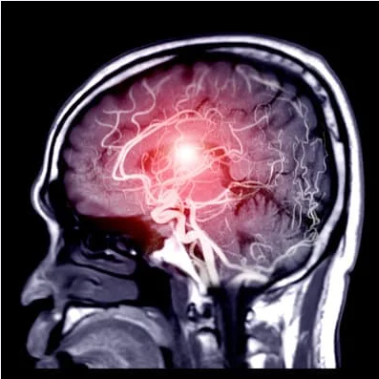

Neurosurgery